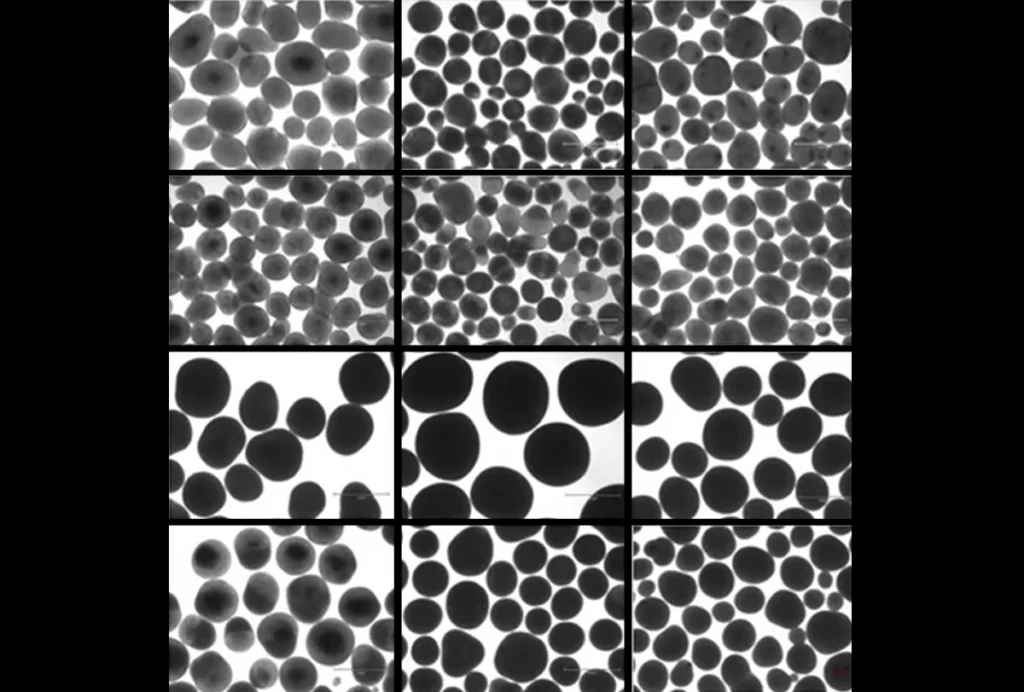

Brain organoid size matches intensity of social problems in autistic people

Overgrown organoids could point to mechanisms underlying profound autism.

Brain organoid size matches intensity of social problems in autistic people

Overgrown organoids could point to mechanisms underlying profound autism.